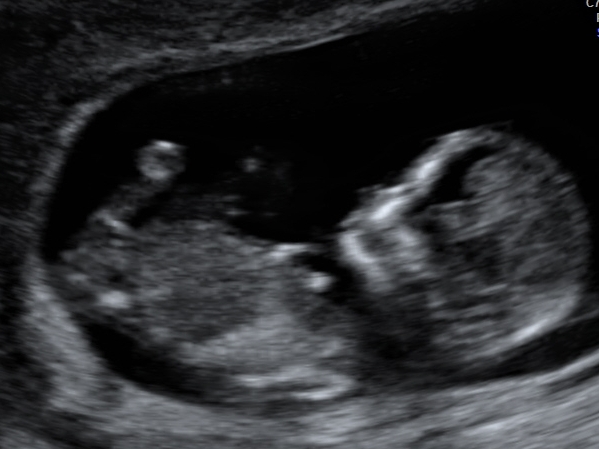

Hi ladies, would really appreciate some defining comments. Got 10 photos from my 12 week scan. I'm nubsessing.

Gestation 12+1

Only 1 (I believe) shows nub but baby is at an awkward angle and didn't stop moving so hard to tell. I'm so sure it's a boy.

I've been told by a couple of mods on nub page they don't think it's nub. 1 said part of leg and got 2 early girl guesses based on another photo.

I can't see a clear nub in these pics. I don't think the bit that looks like stacking is part of the nub as seems too large and too far from where the nub would be.